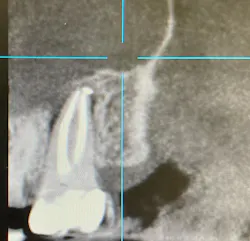

No. 3: Evaluate the radiographs.

Check the radiograph for a lateral defect (lucency) in the bone with little or no apical disease (figure 1). Cases where the disease shows bone loss lateral to the root, but the previous root canal treatment looks to have been filled to the apex, are likely fractures.

No. 4: Evaluate a cone beam CT scan.

If you can use a CBCT scan, it will give you more detail and can be helpful in discerning the pattern of bone loss, although it won’t necessarily show the root fracture itself. Failure of endodontic treatment commonly occurs at the portal of exit apically (unless there is a lateral canal midroot). Fractures are typically present with lateral bone loss (figure 2).